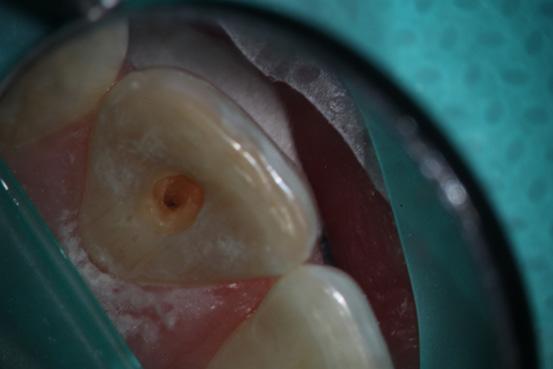

Following administration of local anesthesia and application of a rubber dam, access cavity preparation was performed. Careful exploration of the pulp chamber using endodontic explorer under magnification was employed to locate the canal orifice.

Pre-op intra oral photo of teeth 11, 21

Access cavity of tooth 21